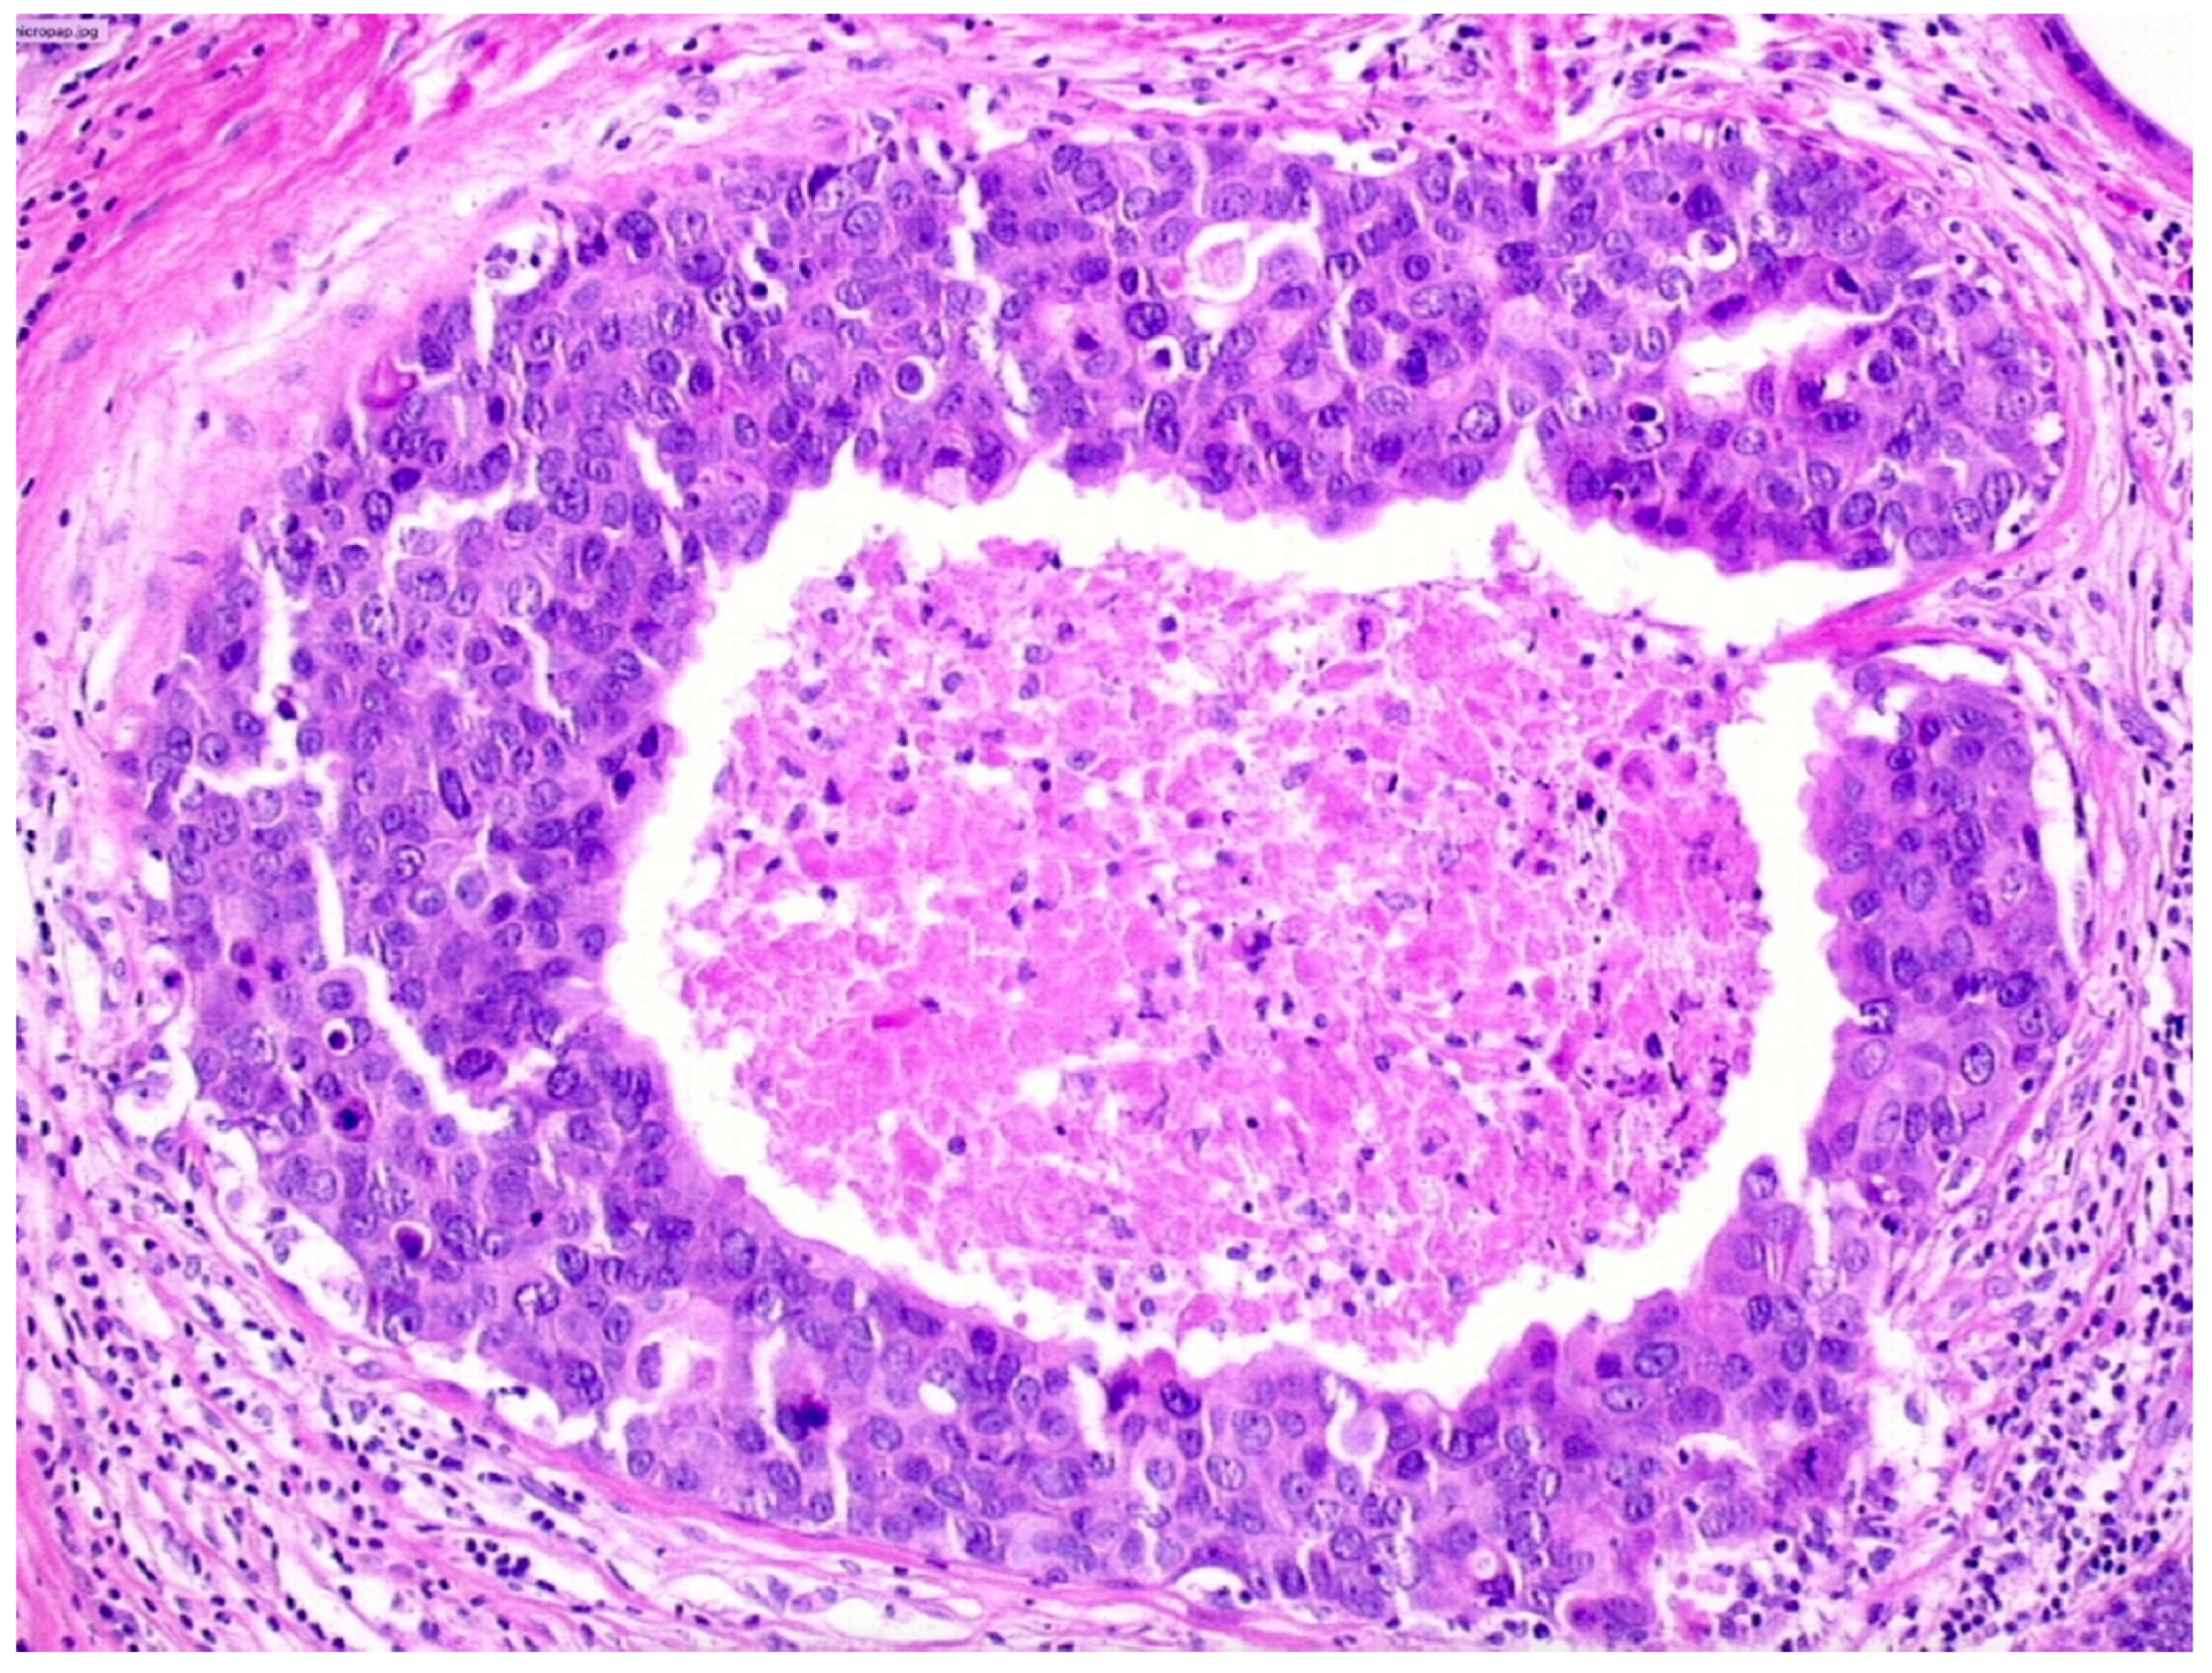

We observed that 408 patients received the diagnosis of DIN1C (low-grade DCIS, Figure 2)—9.6% (39/408) of them were upgraded to invasive cancer. The overall mean diameter of the DIN1C lesions was 22 mm.

We reported, post-VABB, complete removal of the lesion in 159 out of 408 patients with DIN1C diagnosis. Among them, we reported nine cases of invasive carcinoma on surgical specimen, and thus 5.7% (9/159) of low-grade DCIS cases with no residual lesion were upgraded to invasive cancer.

Patients with diagnosis of low-grade DCIS showing complete removal of the lesion experienced a significantly lower upgrade rate when compared to those showing mammographically detectable residual tumor after VABB (p-value < 0.05).

Figure 2. Cribriform ductal carcinoma in situ of low nuclear grade (Hematoxylin & Eosin, 400×).